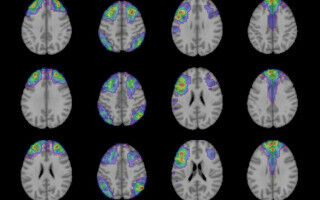

More diversity needed in dementia studies to enhance targeted therapies

A lack of diversity in genomic studies for dementia could limit the effectiveness of targeted therapies across underrepresented populations, finds research by UCL experts. Results from two papers that explore regions of the genome associated with Alzheimer's disease and dementia in African populations will be presented at the Future of Dementia in Africa conference.